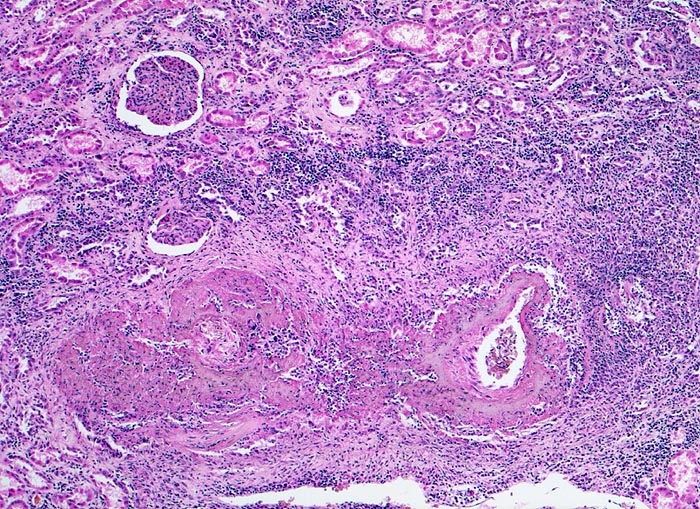

Morphologische Merkmale:

• Unauffällige Glomerula.

• Grössere intrarenale Arterien mit teils zirkulären, teils segmentalen, transmuralen fibrinoiden Gefässwandnekrosen und gemischtem transmuralem Entzündungsinfiltrat.

• Gefässveränderungen unterschiedlichen Alters (frische Nekrosen, Granulationsgewebsbildung, Narben).

• Frische Tubulusnekrosen (abgeblasste Kerne) im Versorgungsbereich der entzündeten Arterien.